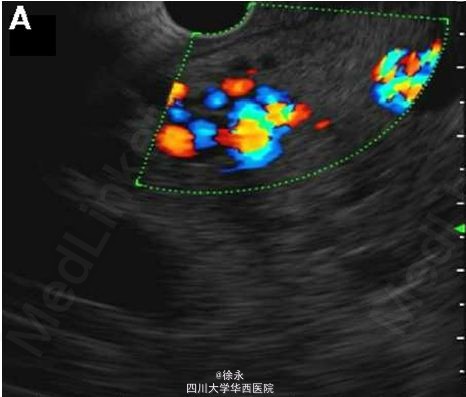

查体:生命体征平稳,无发热,BMI=27kg/m2。可见双侧巩膜黄染,脾大。余无特殊。 辅助检查:血红蛋白 13g/dL,白细胞计数 10400/mm^3,血小板计数 268*10^3/uL,肝功:总胆红素 6.5mg/dL(直接胆红素 4.2mg/dL),ALT 100U/L,AST 183U/L,INR 1.1,总蛋白 7.3g/dL,白蛋白 3.6g/dL。血清病毒及免疫标记(ANA/抗SMA/AMA)均阴性。 腹部CT示双侧肝内胆管扩张,门静脉栓塞。超声内镜(EUS)提示胰头周围广泛海绵状结构,胆总管未显影(图A)。胆管成像(图B)提示,IDUS(图E/F)证实胆囊管多发曲张(白星)压迫胆管(白色箭头)。

考虑诊断:门静脉海绵样血管瘤相关胆管病变 2型糖尿病 高血压 本例患者存在症状,遂境内镜置入胆道支架,作为行外科手术的桥梁。